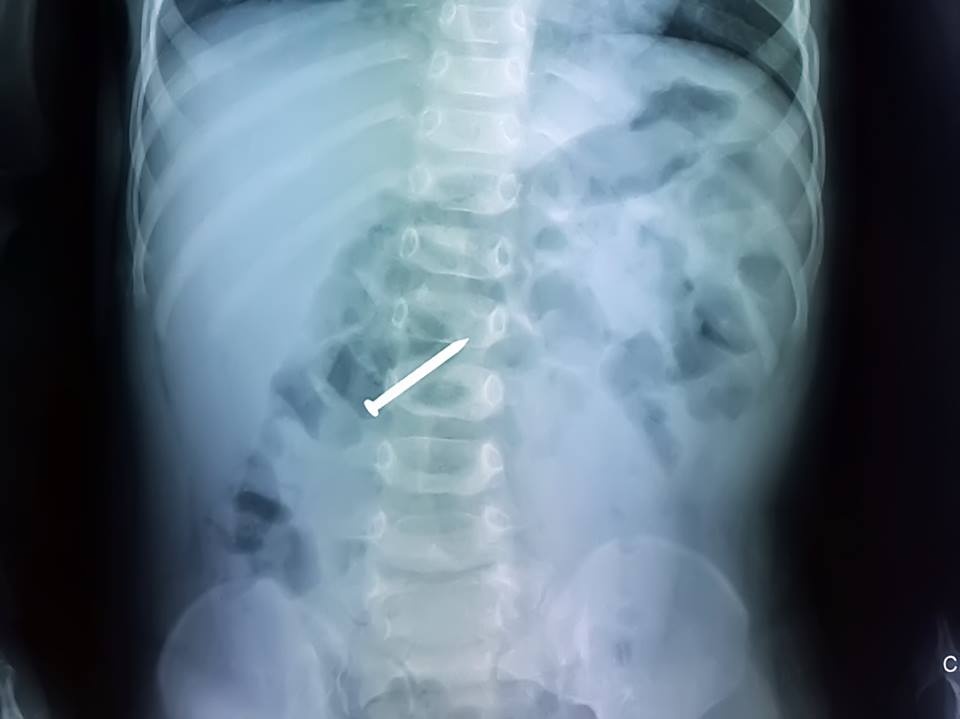

| Ảnh chụp X-Quang cây đinh nằm trong tá tràng bé trai. Ảnh: BVCC |

Tại đây, bé Phi được khám lâm sàng, chụp X-quang. Kết quả chụp phim cho thấy 1 cây đinh nằm ở khung tá tràng. Sau khi hội chẩn nhanh giữa các chuyên khoa, bé được chuyển ngay đến phòng mổ. Các bác sĩ tiến hành gây mê nội khí quản và làm thủ thuật nội soi thực quản - dạ dày - tá tràng để lấy dị vật. Sau khi nội soi, cây đinh dài 3 cm được lấy an toàn ra ngoài. Hiện, bé đã khỏe mạnh, chơi đùa bình thường và được theo dõi tại nhà.